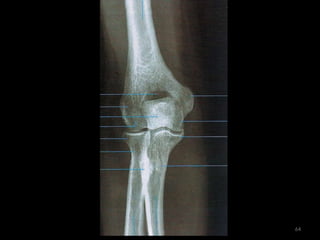

Incidência AP de cotovelo62

63

64